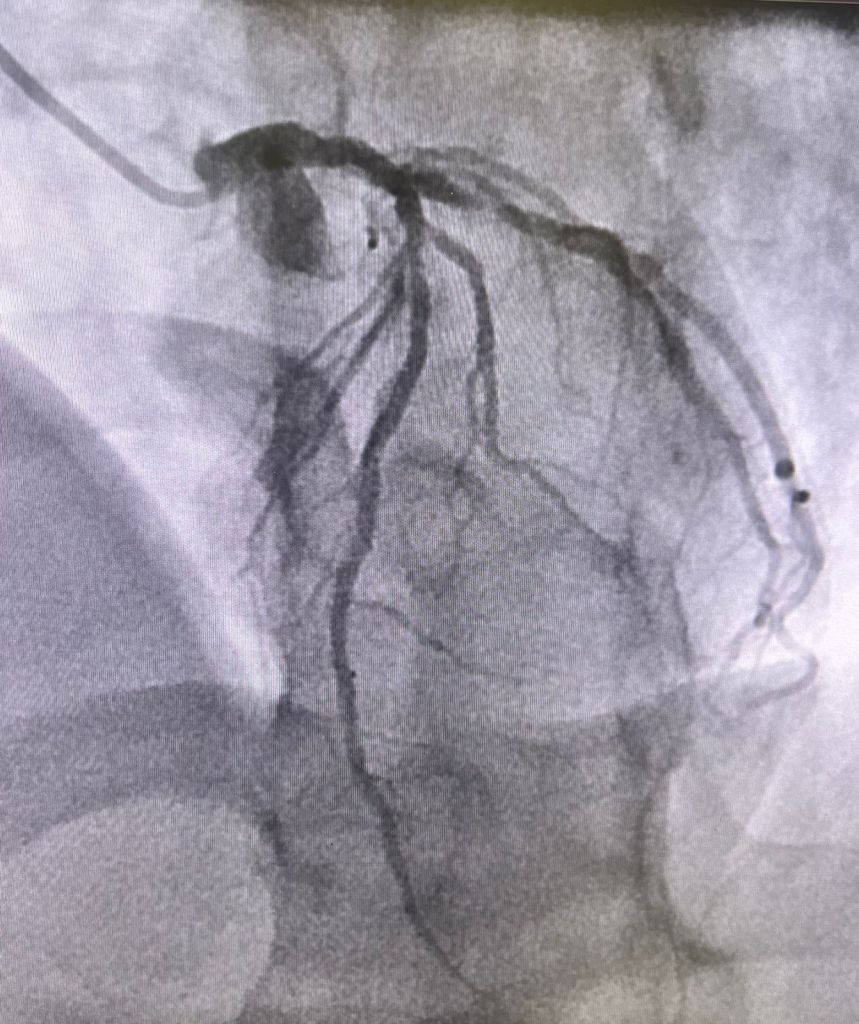

SE showed anterior and inf wall hk, Rest echo 65%ef, post exercise 45%.

LHC showed discrete lesions but diffuse 3 vessel disease, extensive but good targets. Scheduled for cabg next week.

Now at the end of discussion, looks to like need one stent in type A lesion in mid cir, and all the above recommendations, for secondary treatment! Now he will need more anti platelets med for stent!

Bashir, was FFR done on left circ lesion? What was the rationale for doing cath, to begin with?

My point is it’s a non prognostic lesion pt is asymptomatic. Even if it had shown some ischemia or FFR was positive, in asymptomatic pt , would stenting change the risk of future MI or mortality??